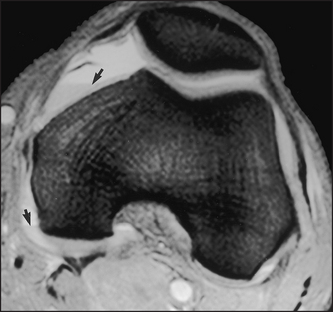

Figures 26.11 and 26.12 show CT scans of changes in the knee.

Figure 26.12 CT scan showing a haemarthrosis of the knee (Resnick DR et al. Internal derangement of joints, 2nd edn. Saunders, 2006.)